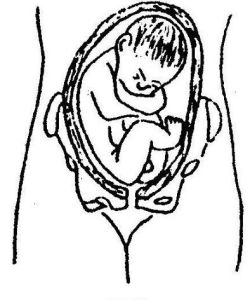

胎位不正

臀位種類左三:足先臀,一支腳或兩支腳向下伸展,比臀部先出。

橫位:當胎兒之長軸和母親之長軸互相垂直,且胎兒之肩膀或手為先露部位,稱為橫位,其機率約為322至1200個生產中,即有一為橫位,當胎兒小於1500公克時或是多胎,特別容易發生,一般有:

(1)胎兒臀位接近母親之骨盆。

(2)胎兒之頭部接近母親之骨盆。